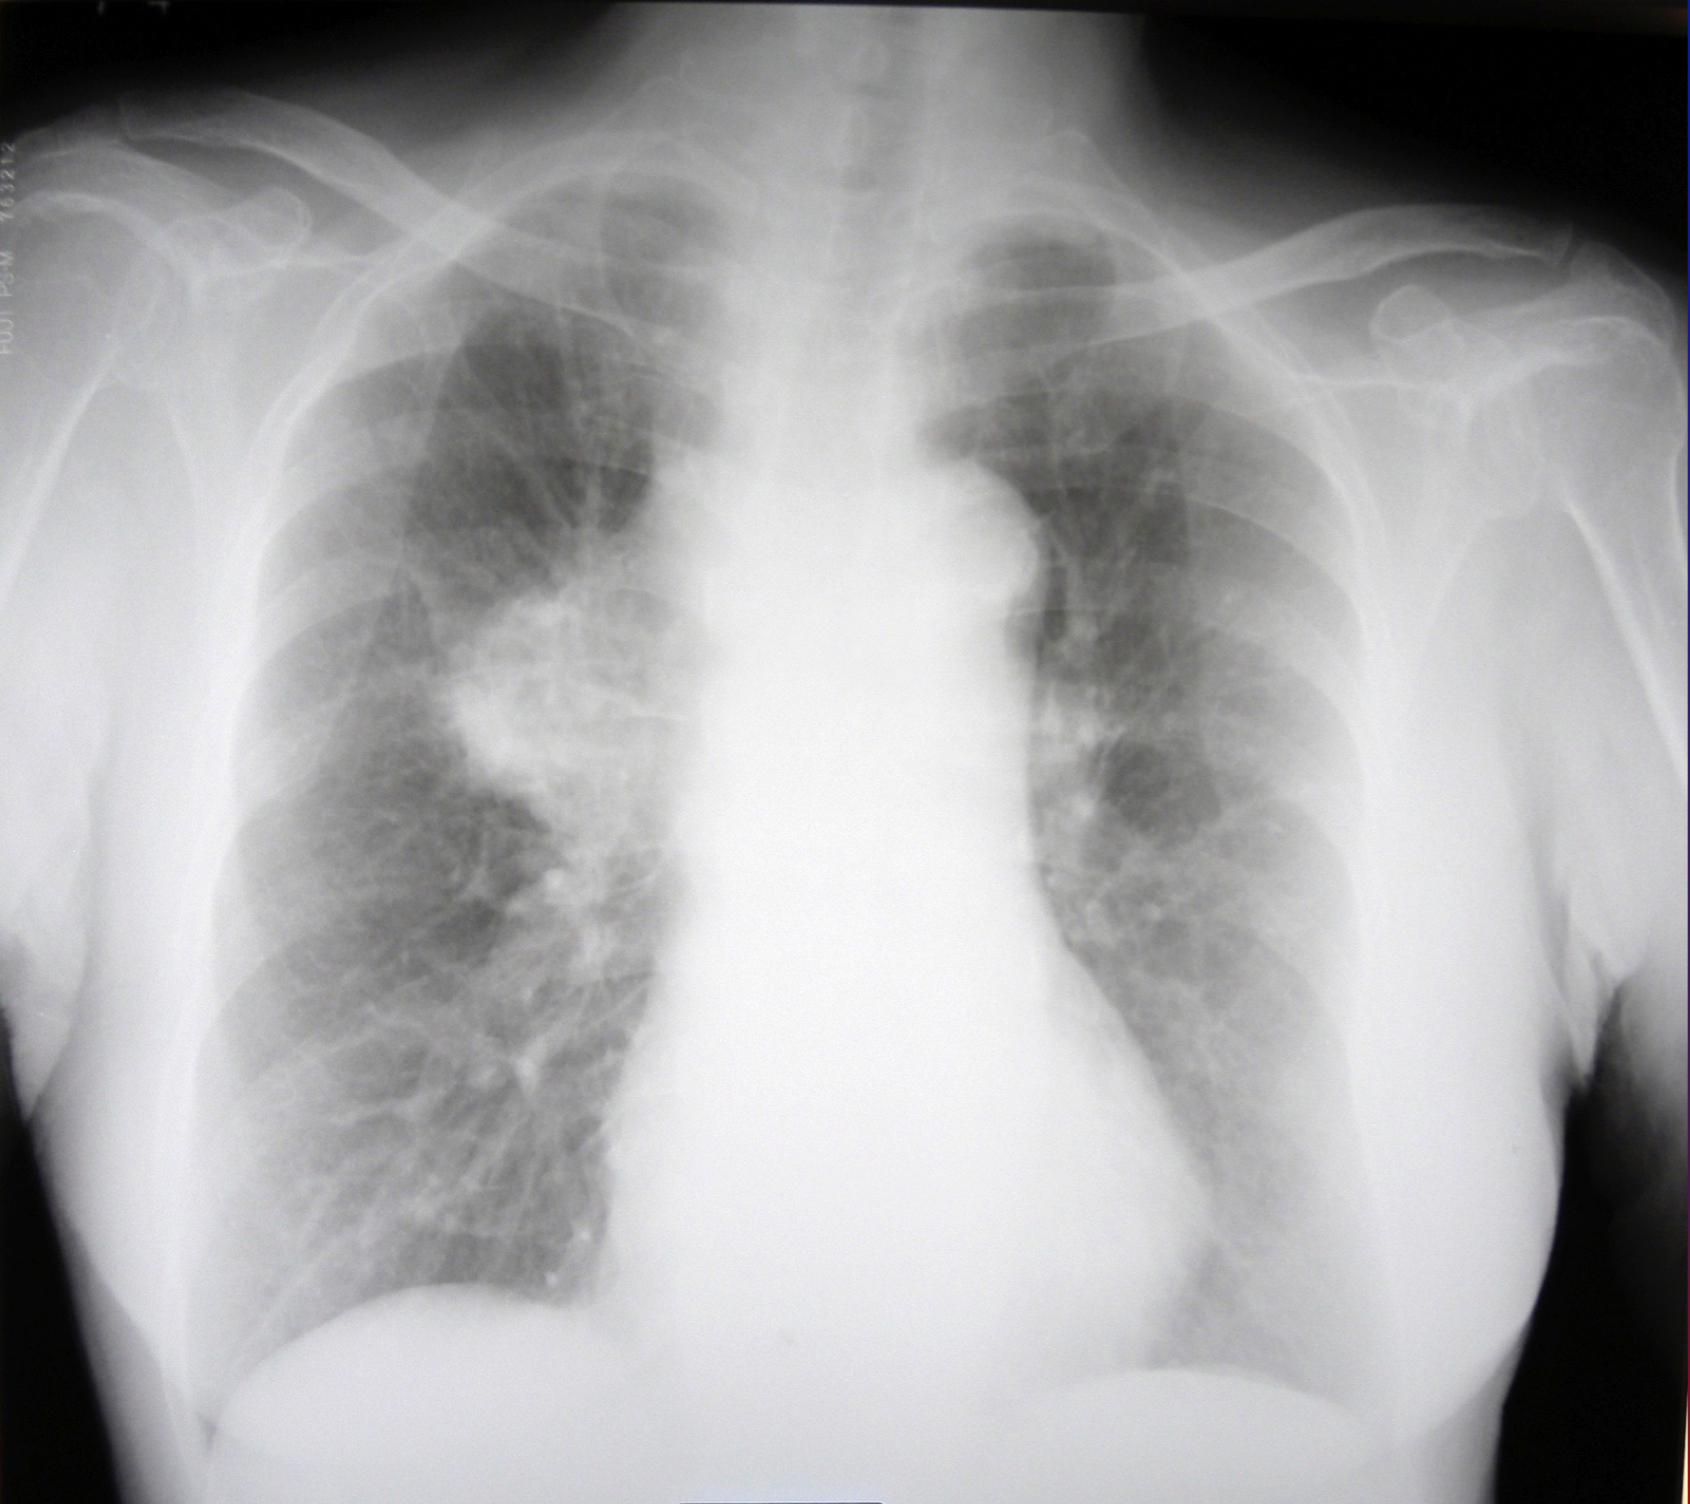

肺がん

肺がん検診

肺がん検診は胸部レントゲン写真を撮影し診断します。

もし異常があれば総合病院等へ依頼し、胸部CTを撮影します。

最近肺がんの発見が増えています。また、胸部CTの精度が上がり、まだ癌か良性病変かの判断がつかないような軽度の病変が見つかることも多くなっております。

残念ながら長期間検診を受診されておらず、発見したときにはかなり進行している場合も多く見受けられます。楽な検査ですので必ず年1回は受診するようにお勧めします。